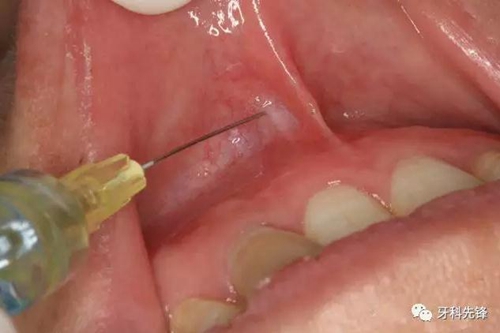

圖4.局部唇、腭側(cè)浸潤麻醉。